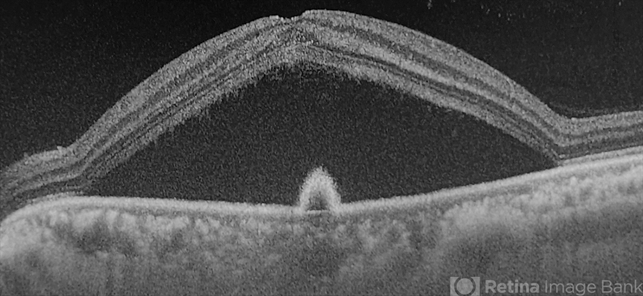

- Central serous chorioretinopathy

- central serous chorioretinopathy (CSCR)

- OCT of a 45 year old man revealing serous macular detachment with a subfoveal PED .